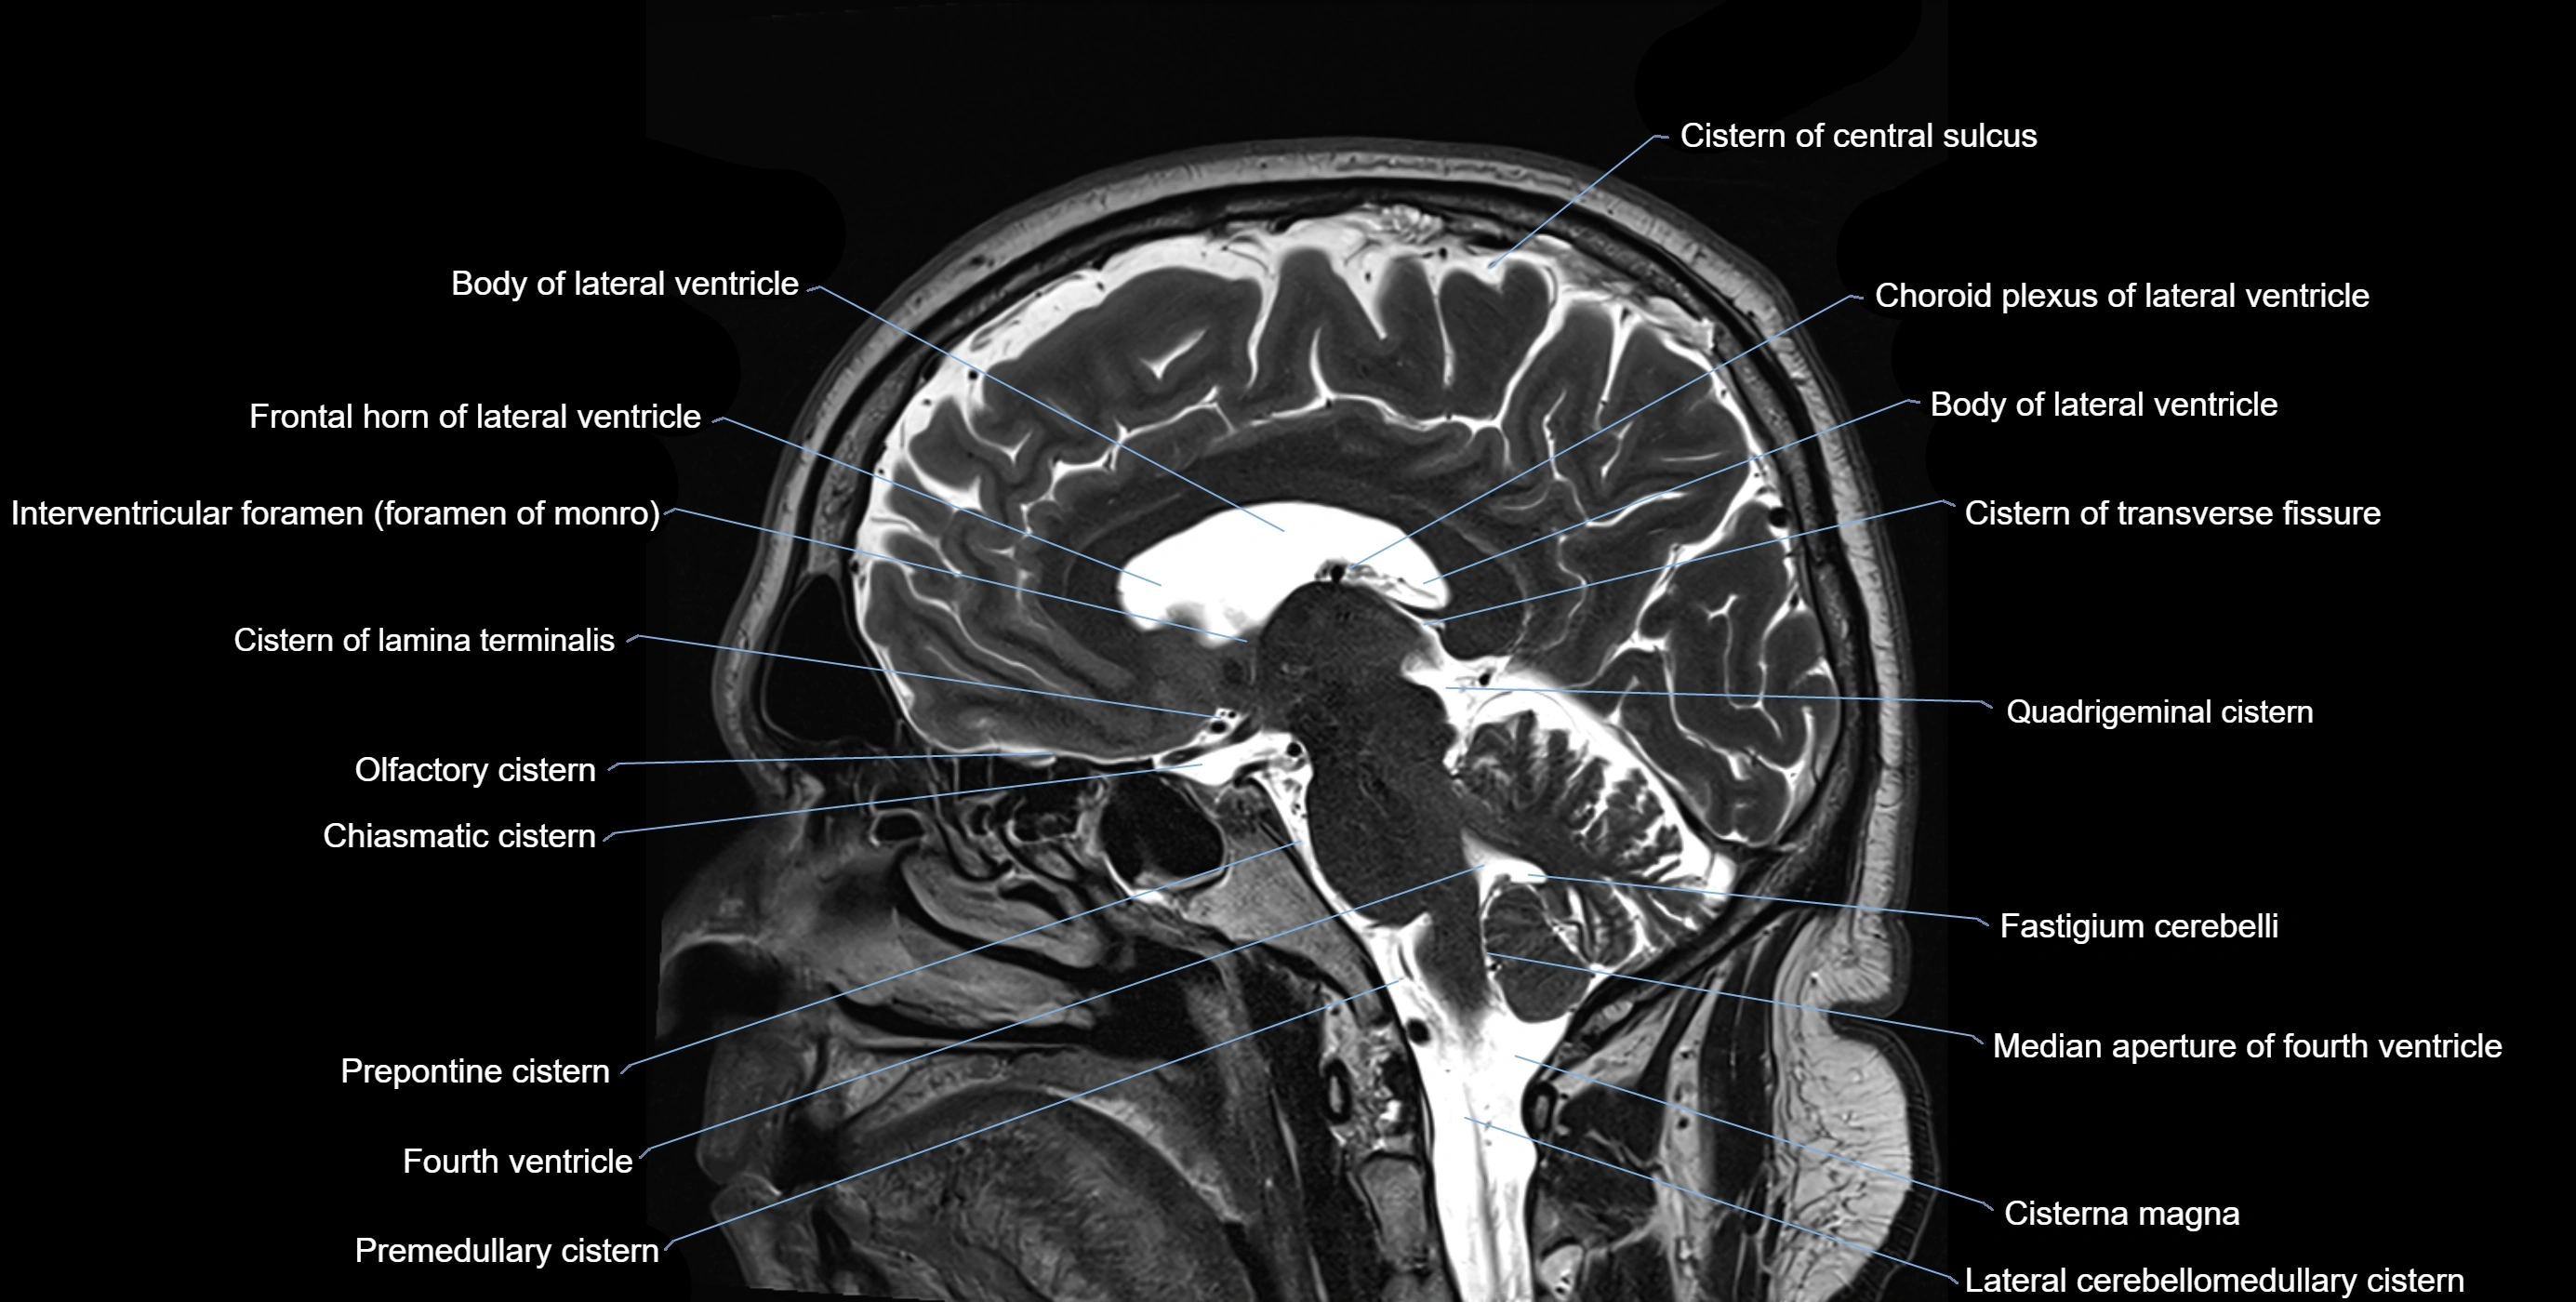

CT image

image